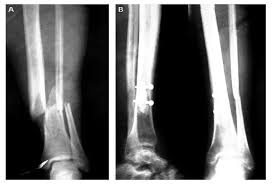

Fracturas de tobillo

Las epifisiolisis del tobillo son las lesiones fisarias más frecuente en niños. En más del 50% de los traumatismos de tobillo en el esqueleto en desarrollo la placa de crecimiento está afectada. Esta elevada incidencia, junto con la posibilidad de dejar graves secuelas, y la dificultad diagnóstica que presentan algunas de estas lesiones justifican su conocimiento.

Diagnóstico por imagen

En todos los casos son imprescindibles las proyecciones anteroposterior (AP) y lateral (L) estándar. Sin embargo, la proyección AP estándar es una proyección oblicua al eje anatómico del tobillo, el eje bimaleolar. Por tanto, es importante añadir una proyección en rotación interna de 20 grados, con objeto de apreciar nítidamente la proyección tibio-peroneo-astragalina.